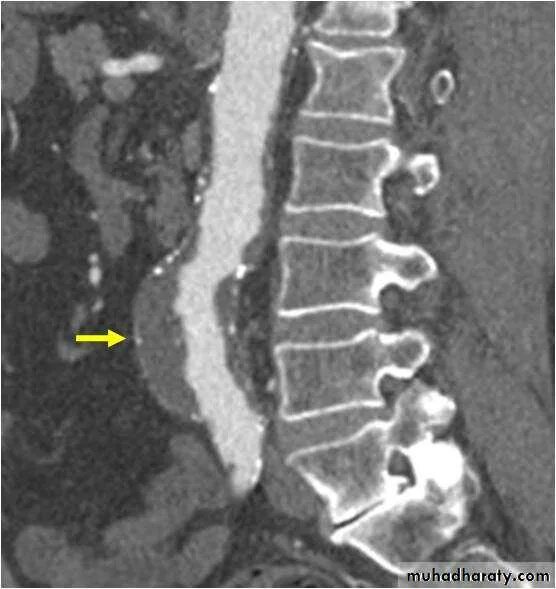

Кальциноз брюшного отдела